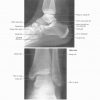

Atlas Giải Phẫu Chi Dưới (Netter) | Bài giảng CĐHA

* Tác giả: Frank H. Netter v6 – 2016